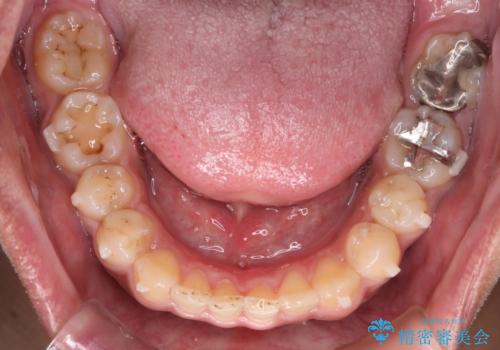

【モニター】インビザライン 前歯の捻れを治したい

- 30代男性

- 矯正装置

- インビザライン

- 治療計画

- 上下の前歯のがたつきを主訴に来院されました。インビザラインで治療可能と判断致しましたので、IPR(歯と歯の間を削る処置)と歯列弓拡大をして

がたつきをとる治療計画を立てました。

マウスピースをしっかり使用していただいたことで、主訴である前歯のがたつきも改善され

リファイメントも1回のみで治療を終了することが出来ました。